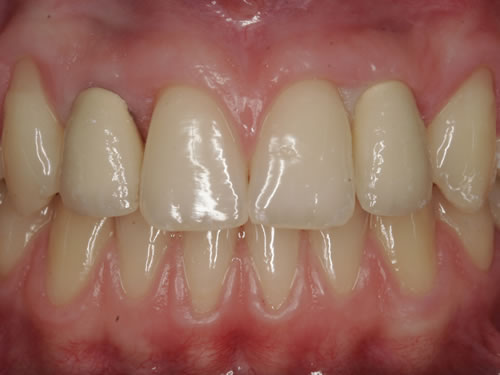

Häufig führt ein Zahnverlust zu einem Verlust von Knochen (Hartgewebe) und der bedeckenden Schleimhaut (Weichgewebe). Besonders im sichtbaren ästhetisch sensiblen Bereich ist es aber notwendig, dass sowohl Hart- als auch Weichgewebe so wiederhergestellt wird, dass im Idealfall das Zahnimplantat mit seiner Krone dem Aussehen des ehemaligen gesunden Zahn entspricht. Als Erfolgskriterien werden aus zahntechnischer Sicht die Form, Farbe und Größe der individuellen Krone angesehen. Aus medizinischer Sicht gibt es wichtige Erfolgskriterien, die die Implantatposition, die Implantatlänge, den Implantatdurchmesser, den Zahnfleischrand im Vergleich zum Nachbarzahn und die Zahnfleischpapillen zwischen den Zähnen beinhalten. Zusätzlich braucht man ein zahntechnisches Labor, das mit der Keramikverarbeitung ein natürliches Aussehen gestalten kann. Nur, wenn alle Parameter perfekt sind, ist das Ergebnis perfekt. Das macht den Einzelzahnersatz im Oberkieferfrontzahngebiet zu einer echten Herausforderung.

Nach der Entfernung von Zähnen kommt es schnell zu Knochenverlust (Resorptionen) und entsprechendem Verlust von Schleimhaut. Die Schleimhaut kann durch bestimmte Operationstechniken wiederhergestellt werden, in dem man freie oder gestielte Bindegewebstransplantate z. B. vom Gaumen entnimmt und das fehlende Material so ersetzt. Das Weichgewebe kann in unterschiedlichen Behandlungsphasen korrigiert werden. In vielen Fällen wird es während der Implantation oder bei der Freilegung verbessert. Manchmal müssen Feinkorrekturen auch nach Eingliederung der fertig gestellten Krone erfolgen, wenn ästhetische Einbußen vorliegen. Häufig hat die Zahnfleischkorrektur auch noch einmal die Änderung der endgültigen Krone zur Folge (Abb. 7.14, 7.15).

Abb. 7.14: Unbefriedigendes ästhetisches Ergebnis nach Implantatversorgung.

Abb. 7.15: Perfektes Ergebnis nach Weichgewebskorrektur und nach Eingliederung der geänderten Krone.

Aus der bekannten Tatsache, dass Knochen- und Weichgewebsverlust nach Zahnentfernungen stattfinden und dass der Verlust grösser ist, je länger die Entfernung des Zahnes her ist, wurde die zeitnahe Implantation überlegt. So kann das Hart- und Weichgewebe durch das neue gesetzte Implantat gestützt und muss nicht zu einem späteren Zeitpunkt ersetzt werden. Für eine Sofortimplantation müssen aber wichtige Kriterien erfüllt sein. Hierzu zählen entzündungsfreier Zahnverlust, gute und dicke Zahnfleischform und keine entzündlichen Veränderungen des Zahnhalteapparates. Wenn diese wichtigen Parameter erfüllt sind, dann ist eine Sofortimplantation möglich. Leider sind die Voraussetzungen nur in sehr wenigen Fällen so, da selten gesunde, entzündungsfreie Zähne entfernt werden. In der Bildergalerie wurde ein tief kariöser Zahn ideal entfernt, ein Implantat als Sofortimplantat eingesetzt und mit einer provisorischen Kunststoffkrone versorgt. Nach Abheilung erfolgte die definitive prothetische Versorgung mit einer Vollkeramikkrone (Abb. 7.16, 7.17).